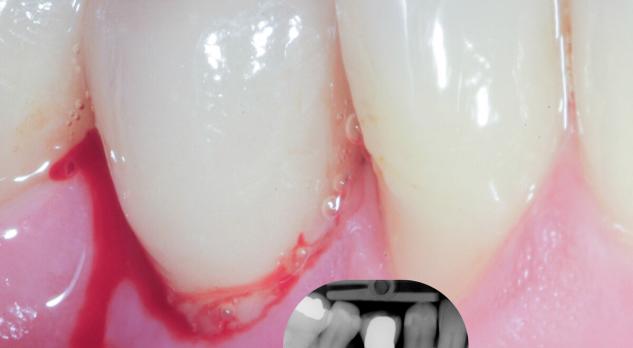

Peri-implantaire ontstekingen, zoals peri-implantaire mucositis en peri-implantitis, vormen een belangrijke bedreiging voor het behoud van tandimplantaten. Deze multifactoriële aandoeningen ontstaan door de interactie tussen bacteriële biofilm, materiaaleigenschappen van het implantaat en de immuunrespons van de gastheer. Risicofactoren als slechte mondhygiëne, parodontitis in de voorgeschiedenis, systemische aandoeningen en iatrogene factoren spelen hierbij een cruciale rol.

In deze nascholing leert u hoe u deze ontstekingen tijdig herkent, voorkomt en behandelt. Blok A behandelt de risicofactoren, preventieve maatregelen en het belang van een goed ontwerp van de prothetische constructie. Blok B gaat in op diagnostiek en behandeling: van het meten van pocketdiepte tot het inzetten van niet-chirurgische reiniging, eventueel gevolgd door een chirurgische aanpak bij peri-implantitis.

U krijgt inzicht in een stapsgewijze behandelstrategie, met nadruk op vroege detectie en het belang van een gestructureerd nazorgprogramma. Na afloop van deze e-learning bent u beter toegerust om peri-implantaire ontstekingen effectief te voorkomen en behandelen, met als doel het behoud van implantaten op de lange termijn.